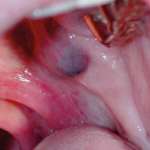

Diagnostica differenziale delle lesioni pigmentate del cavo orale Premium

Le varie localizzazioni e manifestazioni delle pigmentazioni della mucosa orale rendono difficile distinguere quelle attribuibili a malattie sistemiche, a malattie infiammatorie, a neoplasie, a...